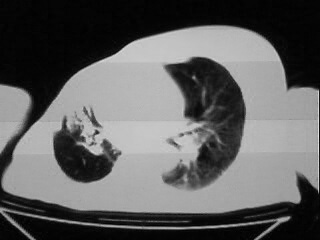

以下是引用随光逐影在2009-2-10 0:07:00的发言:[br]1)右肺放射性肺炎并节段性肺不张?请结合相关病史。2)右侧胸膜肥厚、粘连。3)心包膜增厚(或心包少量积液)。